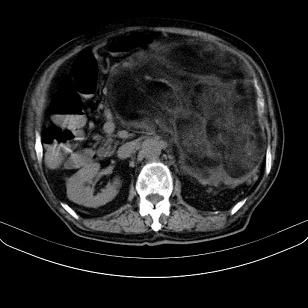

标题: CT21671:男,88岁,左上腹包块 [打印本页]

标题: CT21671:男,88岁,左上腹包块

患者因咳嗽而住院,自觉右上腹包块,无其他不适。

考虑脂肪肉瘤。

腹膜后高分化脂肪肉瘤

小网膜脂肪肉瘤。

左侧腹膜后脂肪肉瘤。